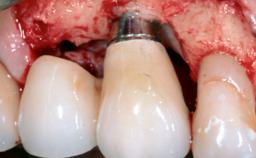

Surgical Management of Peri-Implantitis: Reconstructive Surgical Treatment with Three-Year Follow-up After Treatment

A 70-year-old female patient was referred by her general dentist to the periodontist for assessment and management of an infection associated with implant 36. The general dentist had noted suppuration on probing during examination.